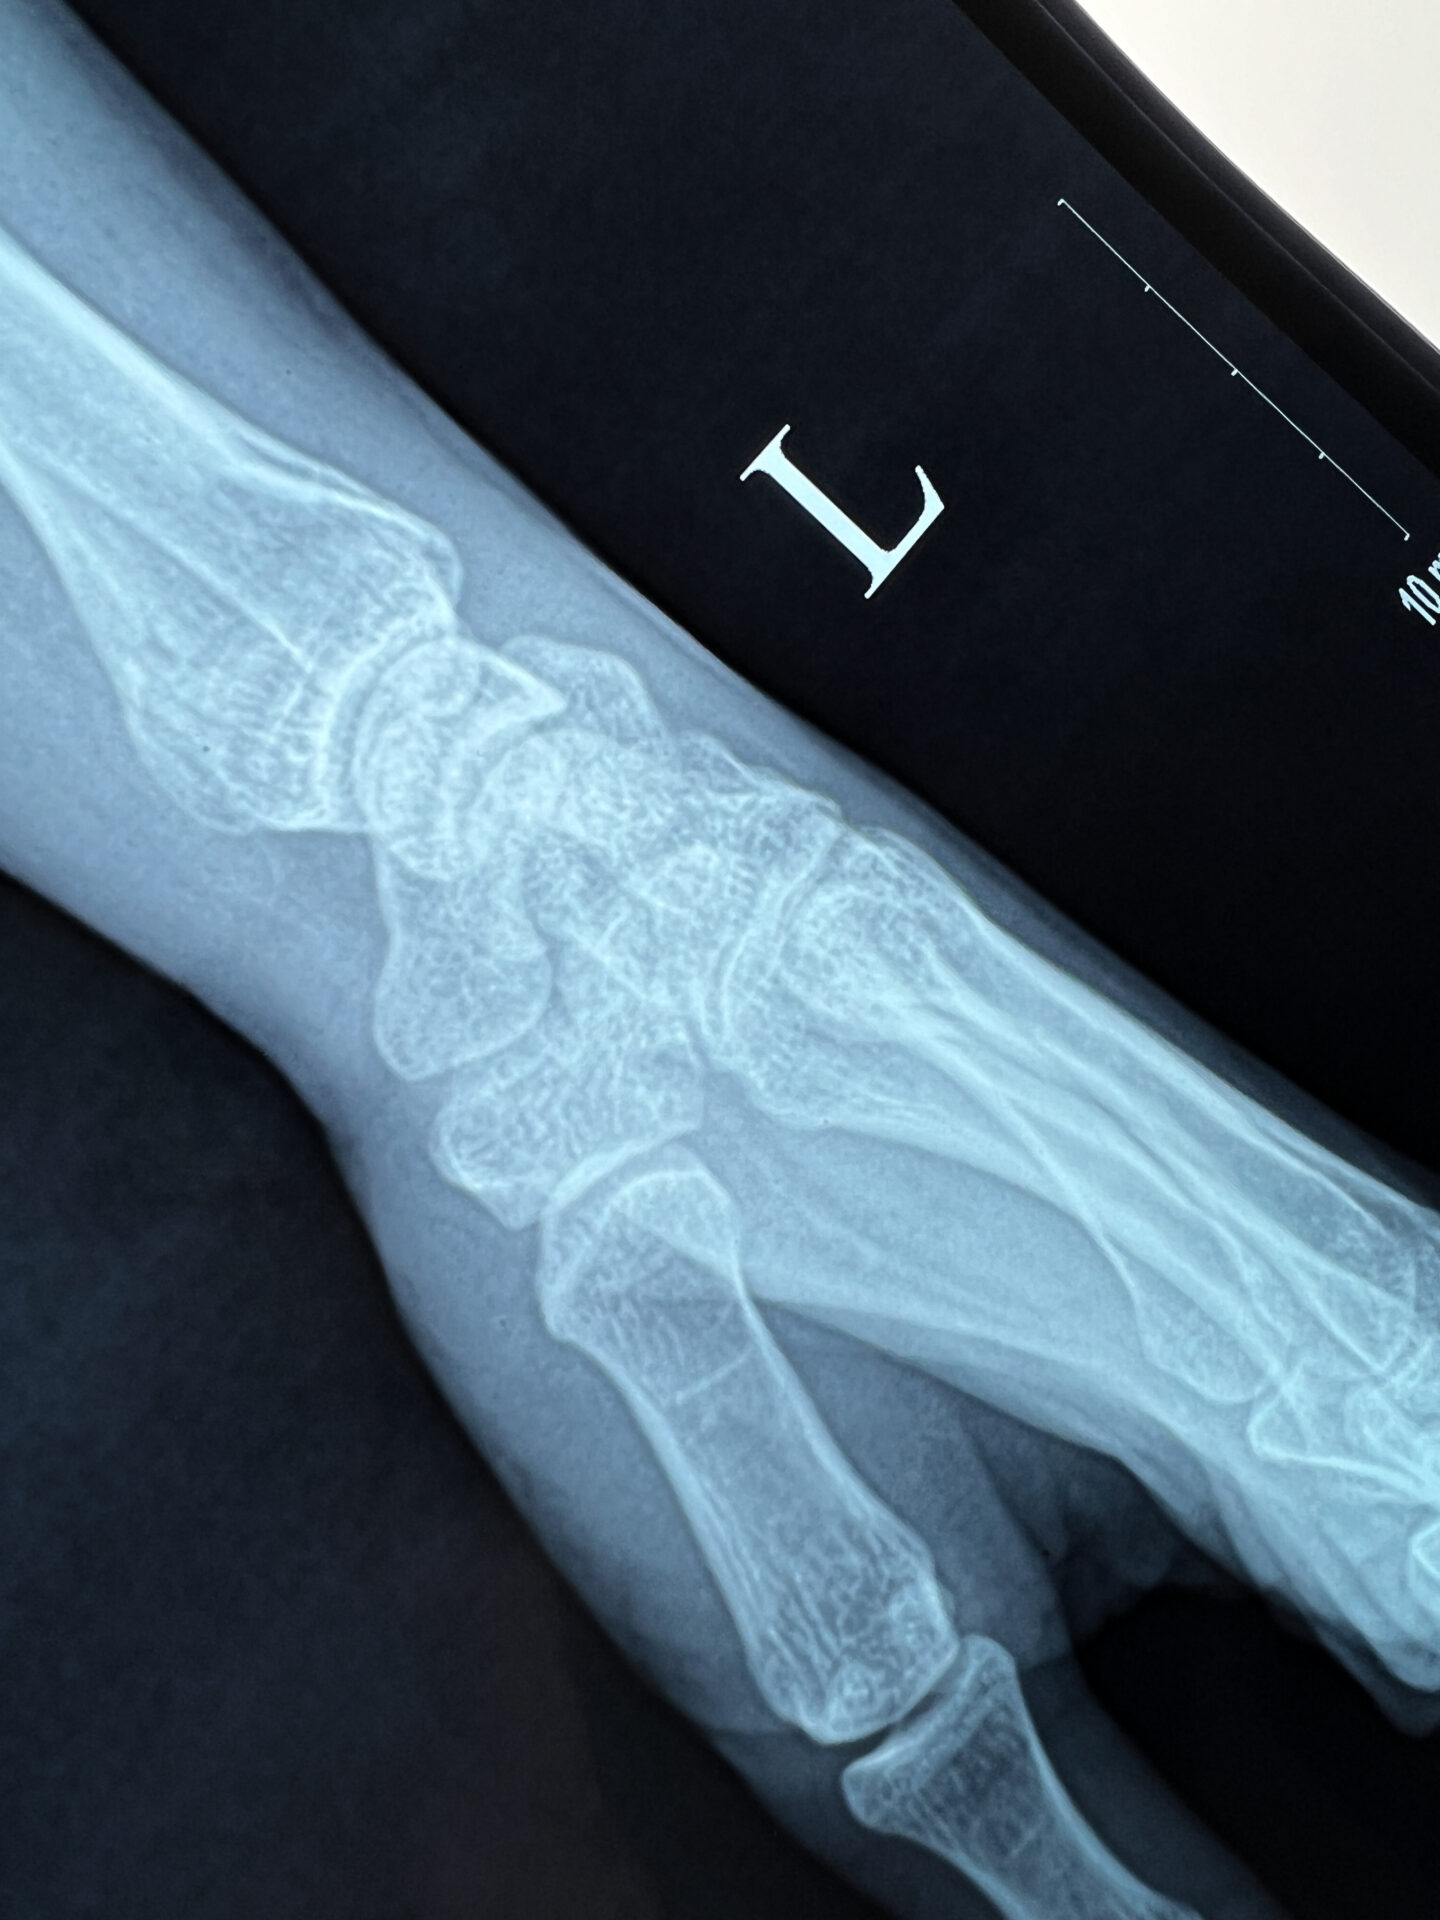

The doctor now speaks through Google Translate on his phone instead of via Mr. Trung, whose translation skills had hit their limit. My verdict: a broken wrist, possibly requiring surgery. The weight of this information, as revealed in a short sentence on an iPhone screen, as well as the uncertainty of my trip, potential surgery, and future plans hit me like a ton of bricks. This time, I can’t stop the tears that come.

I FaceTime my friend, Kate, who luckily for me, is amazing in these types of scenarios. Recalling an Orthopedic surgeon I saw back home a year ago, I suggest, “If I can get him my X-rays, he can advise on surgery and if can continue my trip—I’m still his patient after all.” While FaceTiming me from her computer, Kate calls my doctor’s office and I explain the situation remotely. The receptionist relays that I must email the details quickly so my doctor could review during the few hours he’d be in office the next morning before their week-long New Year’s closure. Over the next 45 minutes, Kate helps me type up my injury details, and I forward her X-rays and wrist photos. Together, though thousands of miles apart, we send the email.

My doctor’s reply came in a little over 24 hours later, while I was exploring Hoi An: “Based on your x-rays, this is a non-op fracture and it is ok to complete your trip in a splint“.